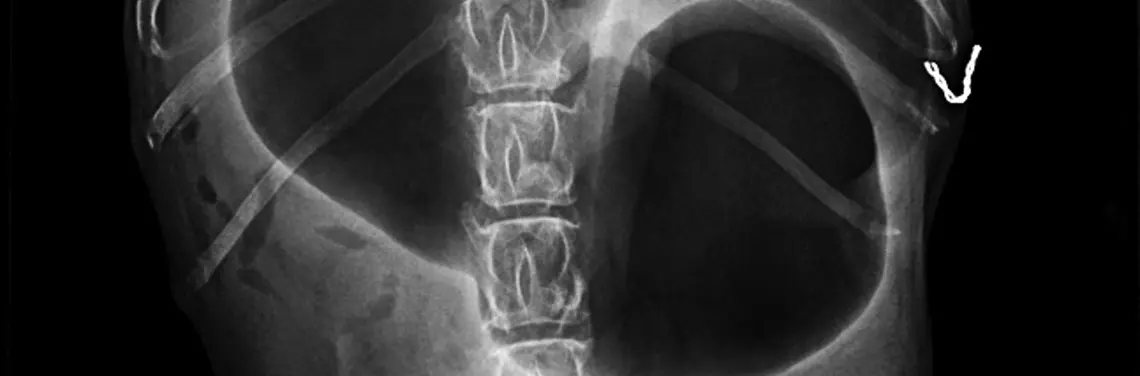

Objawy skrętu żołądka są zwykle bardzo charakterystyczne i w żadnym wypadku nie należy ich bagatelizować. W momencie chociażby cienia podejrzenia, iż mamy do czynienia z rozszerzeniem bądź skrętem żołądka, niezależnie od pory dnia, należy niezwłocznie znaleźć lekarza weterynarii, który zbada klinicznie psa, wykona diagnostykę różnicową (np. RTG jamy brzusznej) i w razie konieczności podejmie się sondowania żołądka lub interwencji chirurgicznej.